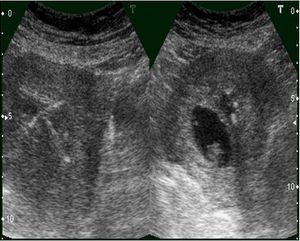

IUCD with Pregnancy IUCD, copper T in uterus with Gestational sacPublished: June 15th 2011 | Updated: